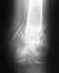

Перелом надмыщелка

Месяц назад сломал вроде как медиальный надмыщелок,отходил в гипсе 1 месяц и неделю.

По итогу один врач говорит,что кость не срастается,но снял гипс.При всем при этом сказал,чтобы я разрабатывал руку и если за 2 месяца она не срастётся,то придётся убирать обломок.Другой же врач говорит,что туда не надо лезть,все должно зажить и также посоветовал разрабатывать.Кому верить и что делать?

• Кликните для загрузки файла IMG-20220717-WA0006.jpg